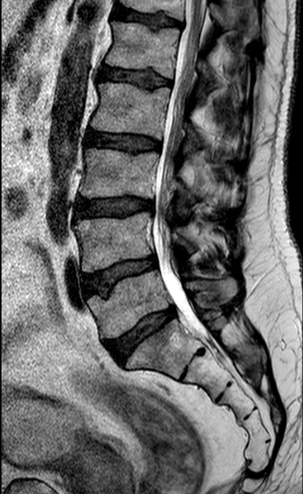

Paciente de 63 años con clínica de claudicación de la marcha.

Preoperatorio